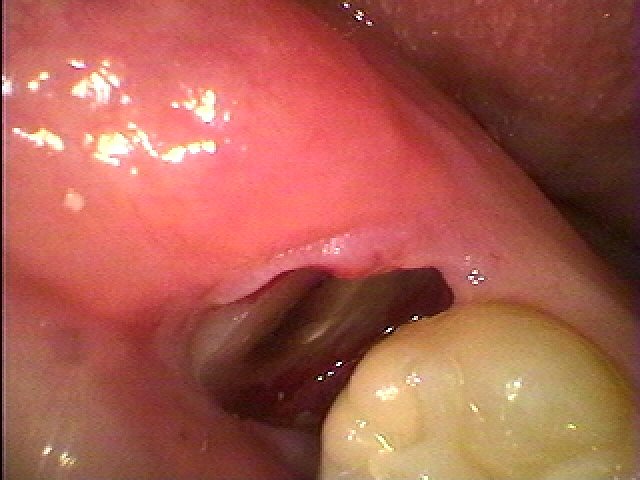

出血は全くありません

根部分を取り出します

出血は全くありません

根部分を取り出します